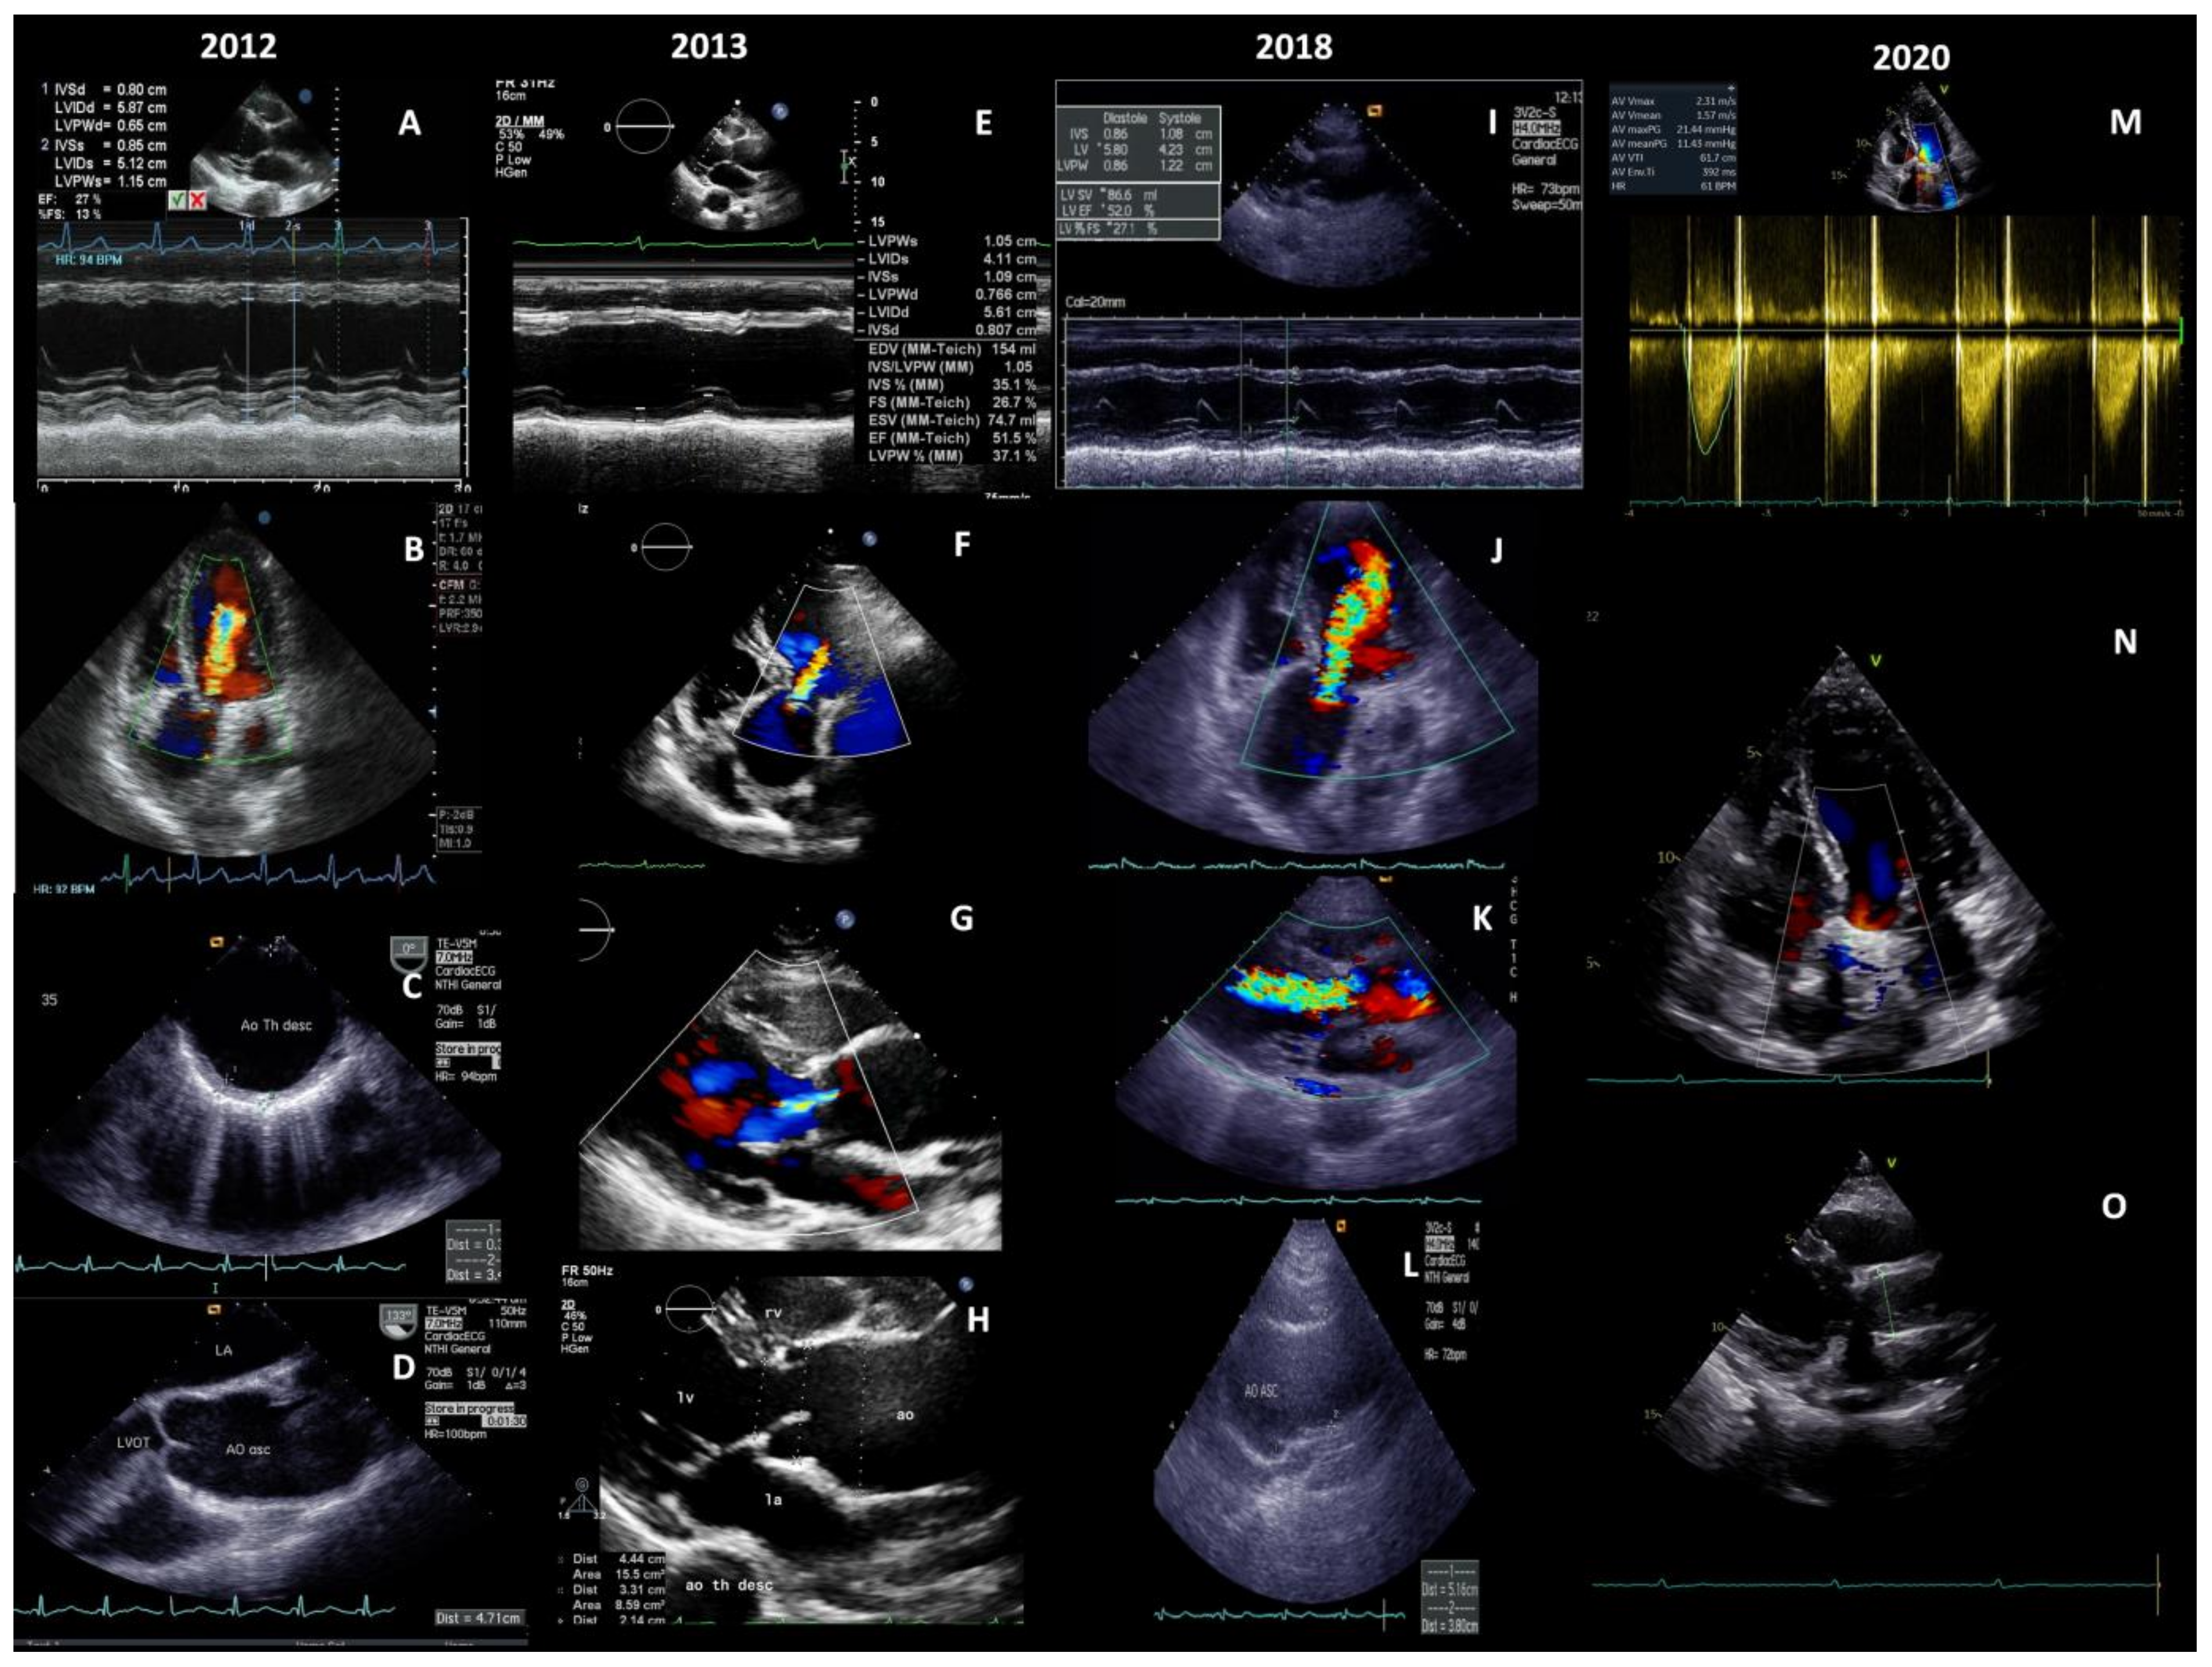

Major Aortic Reconstruction with the Replacement of Supra-Aortic Branches: Successful Surgical Treatment of Takayasu Arteritis Initially Presented as Congestive Heart Failure